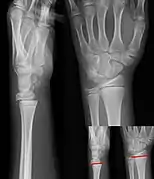

- Salter–Harris I fracture of distal radius.